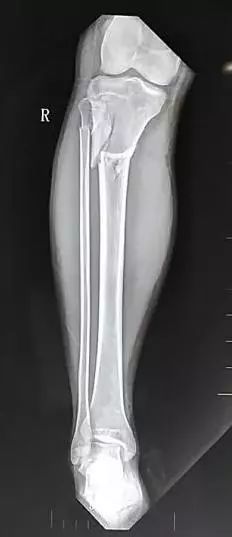

患者,男,56岁,脑外伤及下肢开放伤,急诊手术未使用双氧水,生理盐水冲洗伤口,外固定架固定,伤口游离植皮闭合。骨折及伤口获良好愈合

化繁为简固定法

选择进针点,避开重要结构。

Tips

• 按照多段骨折化繁为简固定方式复位固定近端骨折实现闭合处理。

• 创面新鲜后植游离皮

• 尽快下地走路,生理应力促进骨愈合

• 近端3个月愈合,远端用8个月

• 而后去除外固定架

• 如果使用双氧水会造成骨膜破坏,骨坏死外露,而后骨缺损,需要皮瓣植骨或骨搬运。